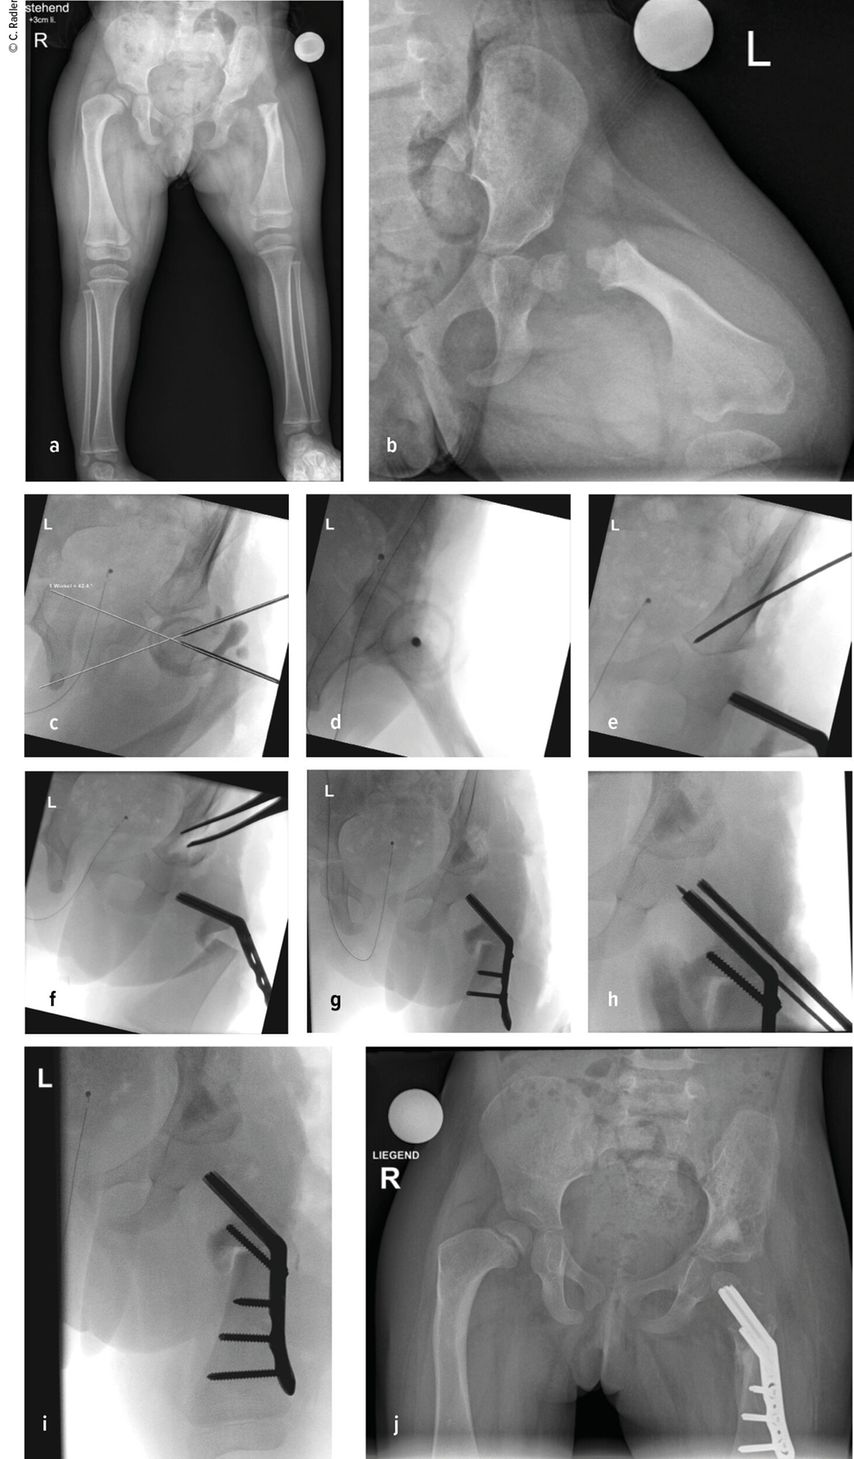

Im Rahmen dieser Operation können auch die Retrotorsion und der Schenkelhalsvarus korrigiert werden. Eine Verlängerung bei nicht optimal überdachter Hüfte führt meist zu einer Subluxation oder Luxation, was eine schwerwiegende Komplikation darstellt, die nur schwer und meist nicht folgenlos zu beheben ist. Auch bei älteren Patienten ist die Überdachung vor einer eventuellen Verlängerung zu überprüfen, wobei besonders ab dem 4. Lebensjahr eine Tripelosteotomie eine bessere Überdachung und Einstellung der Pfanne gegenüber einer Acetabuloplastik erlaubt (Abb.2).

Abb. 2:Versorgung eines kurzen Pfannendachs mittels Tripelosteotomie, um die Hüfte während der Verlängerung vor (Sub-)Luxation zu schützen

Es wird dann auf die Beckenschaufel zugegangen und hier die Apophyse gesplittet und abgelöst. Dieser sogenannte Abductor-Slide entspannt weiter die kontrakte Muskulatur, da vor der Rückvernähung der Apophyse ein Teil des Beckenkamms abgetragen wird. Erst jetzt wird an das Femur herangegangen. Da besonders bei schweren Fällen an der Hüfte nur der Hüftkopfkern sichtbar ist, muss eine Arthrografie durchgeführt werden, um ein Setzen der Bohrdrähte für die Platte zu ermöglichen. Ein erster Bohrdraht wird vom palpierten Trochanter major in das Zentrum des Hüftkopfkernes gesetzt. Ein zweiter Bohrdraht wird etwa in 45° zu diesem wiederum in das Zentrum des Hüftkopfkerns gesetzt. Die Lage des Bohrdrahtes wird im Bildwandler überprüft und kann im seitlichen Strahlengang durch die Überlappung von Hüftkopfkern, Schenkelhals und Kapsel bestätigt werden. Dann kann die Platte schließlich über diesen eingebracht werden. Die Osteotomie des Femurs erfolgt dann in 90° zur liegenden Platte und wiederum in 90° zu diesem Schnitt. Medial muss auch das Periost durchtrennt und releast werden. Nun zeigt sich bereits, wie sehr das Femur verkürzt werden muss, um spannungsfreie Korrekturen zu ermöglichen. Die Platte wird jedoch erst nach der Acetabuloplastik fixiert, um Länge und Rotation korrekt einstellen zu können. Die Acetabuloplastik wurde klassisch als modifizierte Dega-Osteotomie durchgeführt, wobei sich über eine unikortikale Iliumosteotomie („Paley unicortical ilium osteotomy“) eine bessere Überdachung erreichen lässt.

Hierzu wird das Periost des Iliums bis zur Incisura ischiadica und bis knapp oberhalb des Acetabulums abgelöst. Medial wird das Periost im Bereich des Os pubis eingeschnitten, um eine bessere Mobilität des Fragmentes zu erzielen. Es wird dann von knapp oberhalb der Kapsel entlang der Incisura etwa 2–3cm nach proximal gemeißelt. Dann wird ein Bohrdraht gesetzt, der medial auf die Y-Fuge zielt. Entlang des Bohrdrahts wird die Osteotomie schließlich durchgeführt, wobei nur ganz ventral das Ileum medial durchtrennt wird, und hier in Richtung Pubis, wodurch wiederum kaum die mediale Kortikalis überschritten wird. Es kann nun die Osteotomieöffnung entsprechend aufgespreizt und ein Knochenstück aus der Femurverkürzung eingebracht werden. Entsprechend der Überlappung des distalen Femursegmentes in korrigierter Position werden schließlich auch die Resektionhöhe und das Ausmaß der Resektion des Femurs definiert. Nach entsprechender Verkürzung wird über Fixation der Platte schließlich auch die Rotation mit etwa 10° Antetorsion festgesetzt.